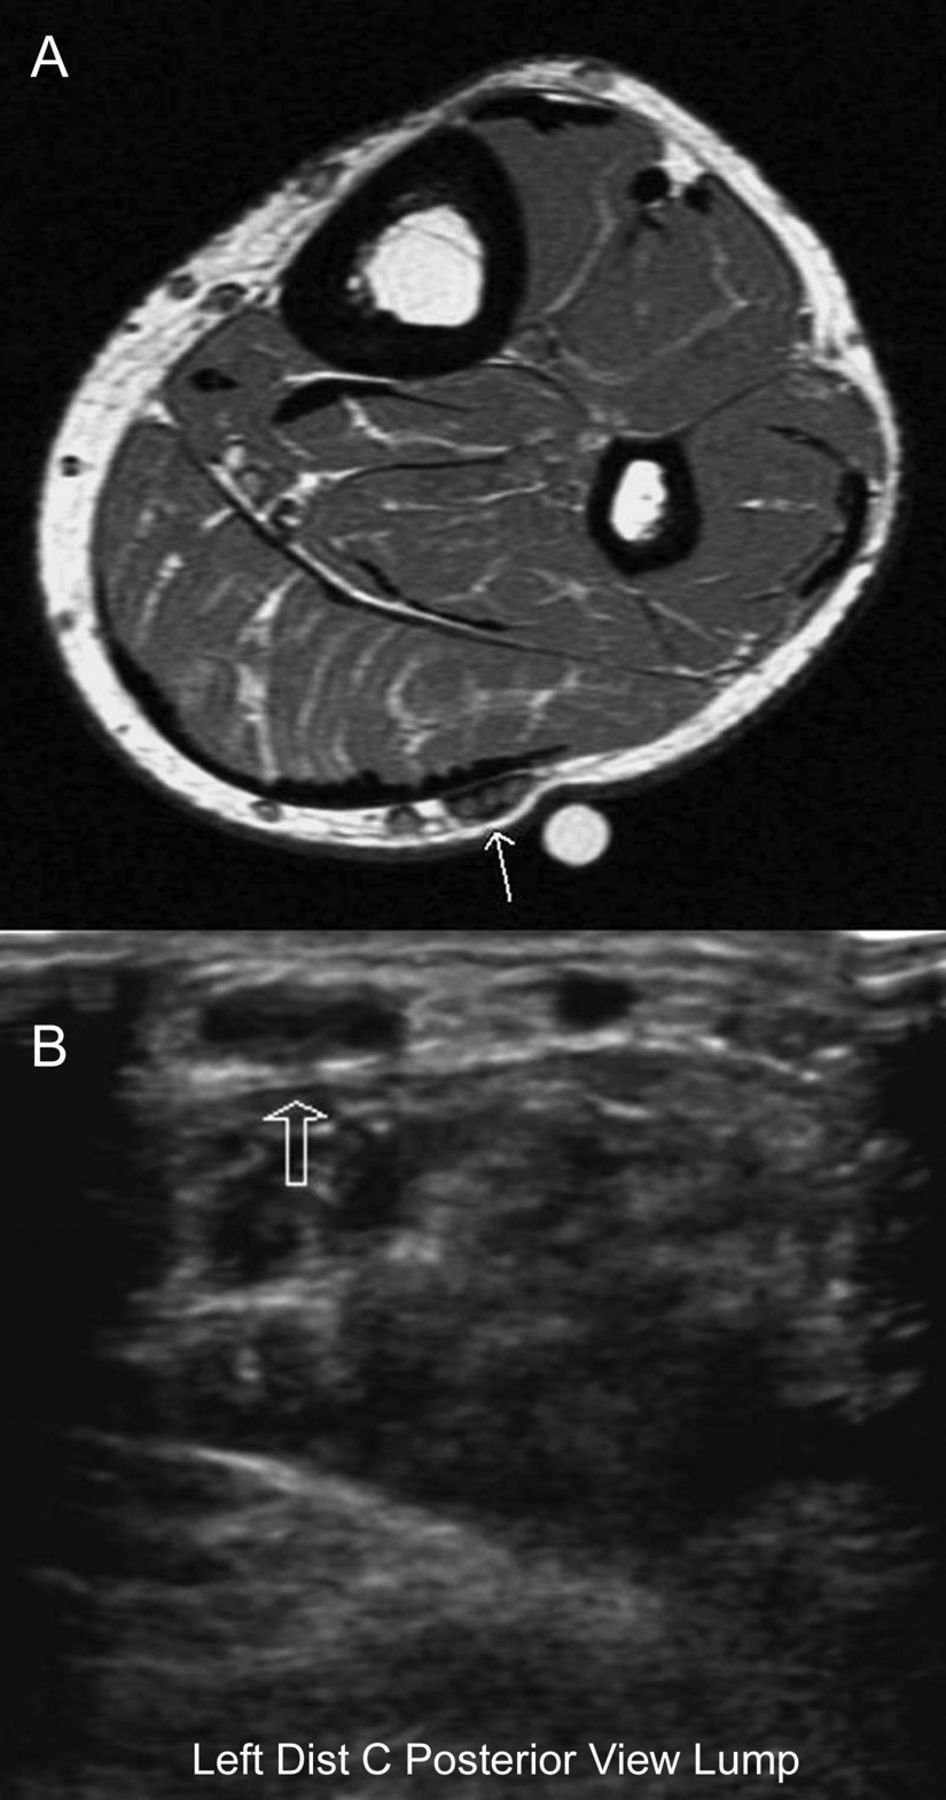

(A)苏木精和伊红显示密度结节周围纤维化,出现让人想起创伤性神经瘤。没有肉芽肿炎症(原始放大40×)。(B) Luxol快速blue-periodic acid-Schiff染色显示神经和再生的无序模式缺乏结节内的有髓纤维(原放大100×)。没有显示:应用CD45和CD68证明小神经外膜血管周围淋巴细胞和巨噬细胞的集合;金宝搏188手机apps - 100应用显示小纤维结缔组织;和上皮膜抗原negative-whorls perineurioma没有见过的特征。